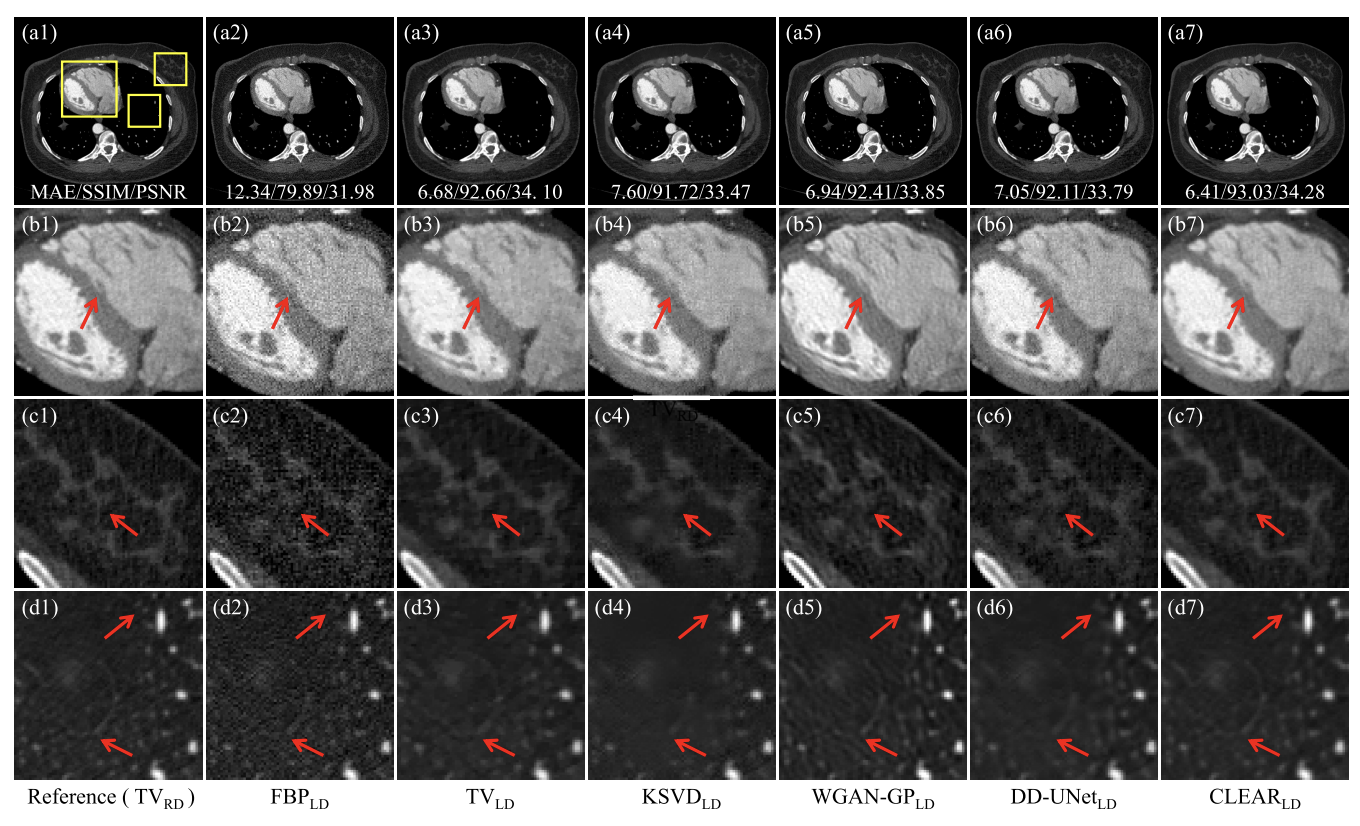

- AAPM 결과

- FBP: 노이즈에 의해 심각히 저하

- KSVD:미세한 특징을 거의 복원X(a4)

- TV: 노이즈 억제 잘 하지만, artifact가 미세구조를 손상( c4)

- DD-UNet: 유클리드 거리 최소화로 인해 흐림 효과가 발생

정량적 분석

CLEAR: 가장 낮은 MAE, 높은 SSIM,PSNR